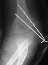

- XRAYS: Radiographic examination of the right upper extremity revealed

a displaced fracture involving the lateral condylar physis exiting through

the substance of the capitellum.